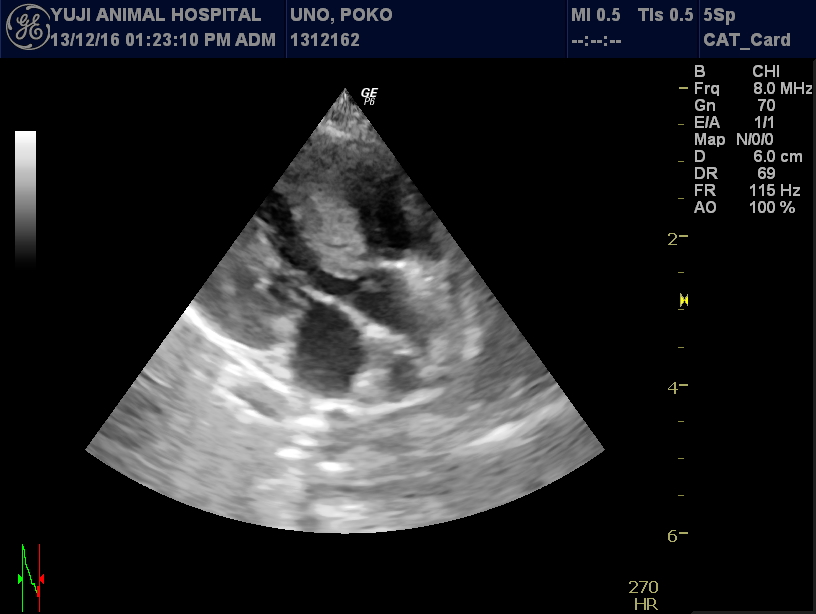

心エコー検査:

この病気の診断において最も重要な検査です。

心臓の筋肉が厚くなっていないかを計測し、内腔(LVIDd)が狭くなっていないかも計測します。また収縮機能の亢進(FSの上昇)や、カラードプラにより拡張機能の障害(E派の上昇)も診断します。弁(心臓の部屋と部屋の扉)が引っ張られたり、逆流がおきていないか(SAM)も同時に確認します。